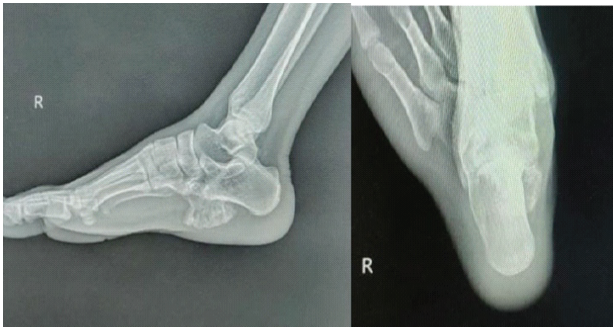

A 19‑year‑old male student presented with complaints of swelling, pain, and discomfort on walking over his right heel, with onset approximately 2 years prior. There was no preceding history of trauma, constitutional symptoms, or similar swellings elsewhere in the body. Examination revealed a solitary 5 × 5 cm bony hard swelling over the inferomedial aspect of the right calcaneum, non‑tender, non‑mobile, and overlying skin was normal in appearance, without redness, warmth, or ulceration. Movements at the ankle and subtalar joints were preserved. Plain radiographs of the right ankle lateral and calcaneum axial views demonstrated a well-defined pedunculated bony outgrowth arising from the inferomedial surface of the calcaneum, showing cortical and medullary continuity with the parent bone (Fig. 1).

Figure 1: X‑ray of right calcaneum showing pedunculated bony outgrowth.